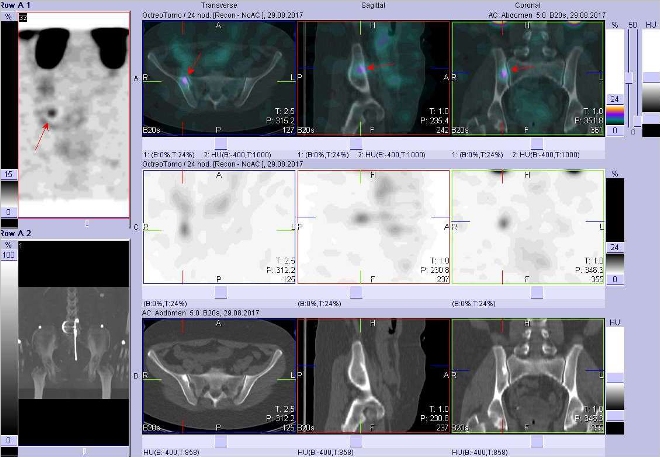

/ Obr. č. 4: Fúze obrazů SPECT a CT. Vyšetření 24 hod. po aplikaci radioindikátoru. Zaměřeno na ložisko v kosti kyčelní vpravo těsně u SI skloubení.

Pozorujeme ložiska zvýšené depozice radioaktivity v levé pažní kosti proximálně a v pravé kosti kyčelní – nálezy jsou suspektní z generalizace neuroendokrinního nádoru do skeletu. Dále je zvýšená depozice radiofarmaka v oblasti pravého laloku štítné žlázy, přičemž je pacientka po levostranné lobektomii štítné žlázy – nález atypický, vhodné endokrinologické vyšetření.

U 49leté nemocné jsme scintigrafickým vyšetřením pomocí Octreoscanu zjistili suspektní kostní metastázy v levé pažní kosti a pravé kosti kyčelní. Dále je atypický nález v pravém laloku štítné žlázy, je vhodné endokrinologické došetření.